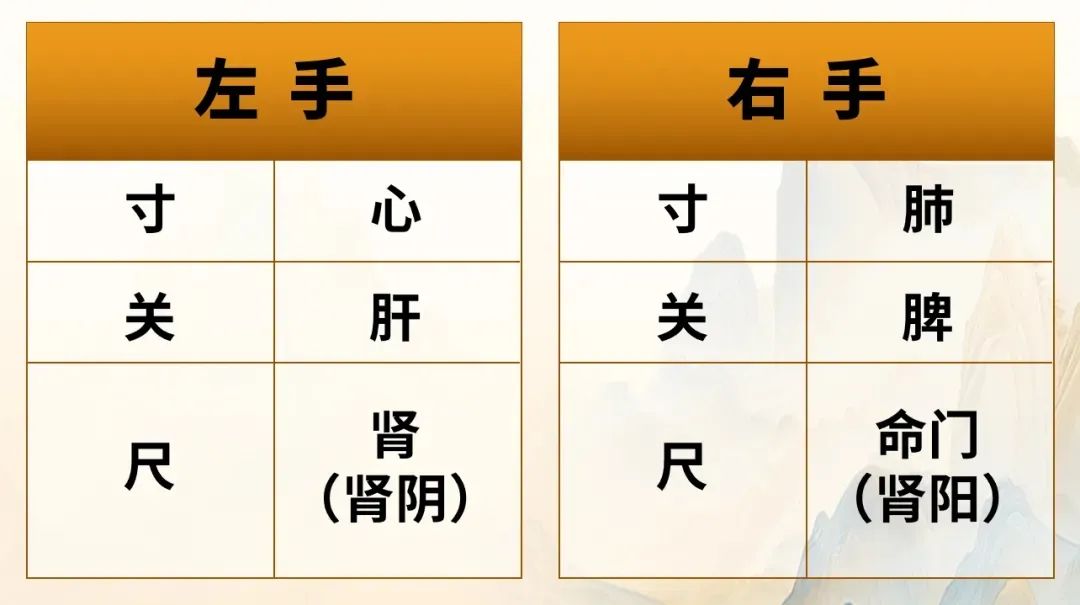

诊断方法:比脉法+夺心术

双手诊脉,主打快准!

比脉法:通过脉搏强弱、快慢温度等快速诊断,不说话知其病证。

夺心术:无需患者开口,知其不可说之事,断其根本病因,直击患者内心!